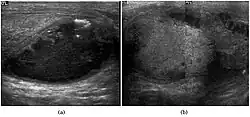

The incidence of infertility is decreased if surgical orchiopexy is carried out before the 1–3 years but the risk of malignancy does not change. Because of the superficial location of the inguinal canal in children, sonography of undescended testes should be performed with a high frequency transducer. At ultrasound, the undescended testis usually appears small, less echogenic than the contralateral normal testis and usually located in the inguinal region [Fig. 29]. With color Doppler, the vascularity of the undescended testis is poor.

Fig. 29. Undescended testis. (a) Normal testis in the scrotum. (b) Atrophic and decreased echogenicity of the contralateral testis of the same patient seen in the inguinal region.